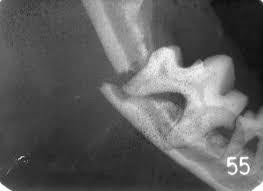

こうなってしまった、別のワンちゃんの顎のレントゲンです。

歯の根元周囲の顎の骨が赤い矢印の部分で溶けてなくなっています。

こうなると歯はぐらぐらして抜けてしまいます。

結局、歯の病気は最後は顎の骨が溶ける病気と考えて下さい。

(レントゲン写真 ヤフー画像より引用)